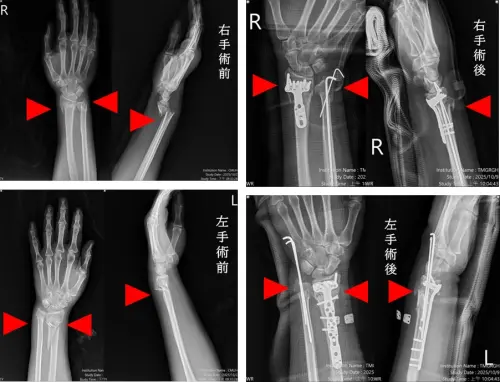

市醫3主治協同手術 多處骨折僅1小時修復創紀錄

台中57歲婦人因交通事故雙手多處骨折與脫位,台中市立老人復健綜合醫院確診為粉碎且複雜性骨折,啟動「多主治醫師協同手術機制」,由骨科部蘇伯翰、江晟弘、毛睿...